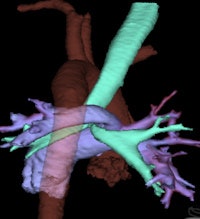

X-ray exams should be ordered first for children who have swallowed a foreign object impeding breathing or who have asthma. Radiographs are also recommended for children suspected of having congenital cystic lung disease. However, contrast-enhanced CT is used in patients with persistent symptoms of congenital lobar emphysema to rule out extrinsic vascular compression and to depict the anatomy of the affected lobe and degree of compression.

Vascular rings are congenital anomalies that may be identified with upper gastrointestinal series and echocardiography exams. Cross-sectional imaging with multiplanar and 3D volume rendering reconstructions can help clarify the anatomy. A CT angiography exam may be the scan of choice over MRI because its images show higher spatial resolution of the small caliber vessels and airways, according to de Lange. There also is no need to sedate the patient with this procedure.